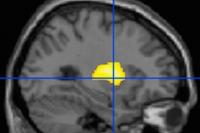

Heavy Cannabis Users Have Lower Dopamine Release in Brain

Heavy users of marijuana had lower levels of dopamine in a brain region involved in working memory, impulsive behavior, and attention, according to a study from the Department of Psychiatry.